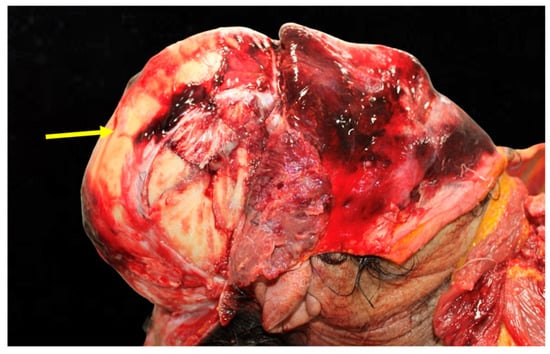

Figure 1. Analysis of head trauma in the frontal region. This image depicts significant bruising and lacerations on the frontal area of the skull. The external injuries suggest a high-energy impact consistent with head-on collisions.